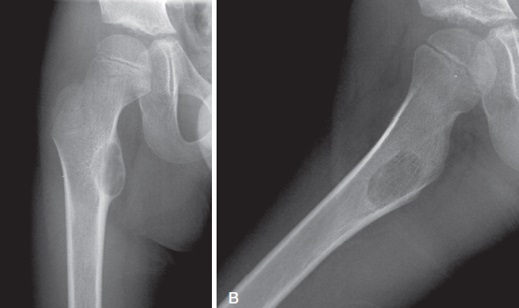

23

Qual diagnóstico?

Lesão lítica, acometimento epifisário Osso maduro dx: TCG

24

Lesão lítica, expansiva com acometimento da epifise Osso maduro Dx: TCG